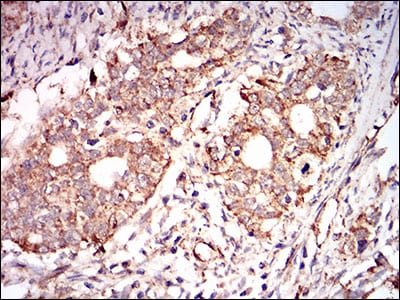

分类: 科研抗体货号: 30599别名: CDA02; EIF-2A; MST089; MSTP004; MSTP089应用: WB,IHC,FCM反应种属: Human,Mouse,Monkey,Rat